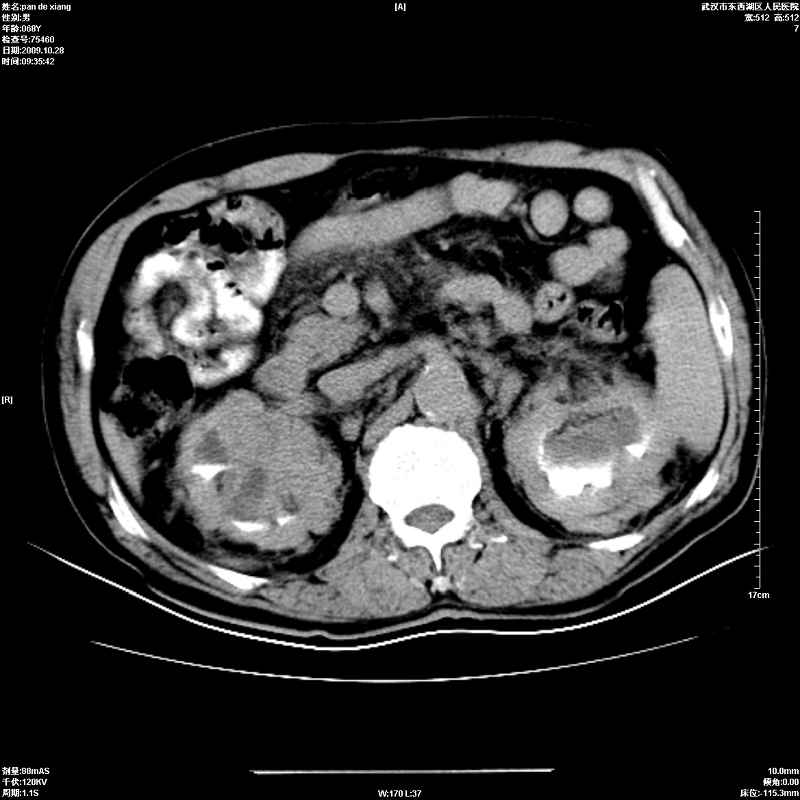

以下是引用杀毒软件在2009-10-28 20:41:00的发言:[br]结合临床考虑---白血病双肾改变或淋巴瘤。

以下是引用zxl51642在2009-10-29 9:59:00的发言:[br]结合临床“单克隆免疫球蛋白血症”,考虑双肾为继发损害并肾功能不全(尿中大量igg及少量iga、igm等大分子免疫球蛋白滤出所致继发损害),椎前软组织肿块为髓外造血。与浆细胞瘤有区别,平扫时有战友说的很清楚。